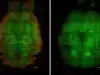

BRAIN VASCULATURE

Scientists achieve striking reversal of Alzheimer’s in mice using nanotechnology

Scientists achieve a striking reversal of Alzheimer’s in mice using nanotechnology. The therapy restores blood–brain barrier function, rapidly clears toxic amyloid-β proteins, and improves cognitive performance. Researchers say this breakthrough highlights the importance of vascular health and offers hope for future human treatments, potentially slowing disease progression and enhancing current therapies.